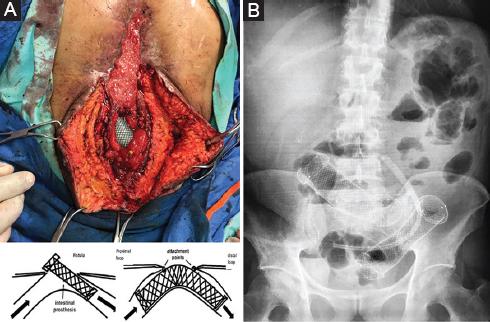

Se decide una tercera intervención en el hospital de tercer nivel, el 9 de abril, desmantelando la anastomosis previa, la cual presentaba dehiscencia de más del 70%. Se decide hemicolectomía derecha con la finalidad de prevenir fugas debido a la pobre irrigación del remanente de ciego y de colon ascendente. Se realiza anastomosis transverso-yeyuno. No es posible separar el yeyuno adherido al colon sigmoides (Fig. 2). Al cuarto día se produce fuga de la anastomosis por acodamiento en el colon sigmoides y aumento de la presión (Fig. 3). Para limitar la contaminación de la cavidad, se coloca un sistema de cierre asistido por presión (VAC) (Fig. 4), lo cual permite el cierre de la línea media de la herida en cuatro sesiones de VAC, dejando únicamente la dehiscencia de anastomosis como una fístula enteroatmosférica aislada. Debido a la condición del paciente (desnutrición, sepsis, desequilibrio hidroelectrolítico, abdomen hostil) no son posibles más cirugías, por alto riesgo de perforación y desvascularización. El aislamiento de la fístula ayudó a mejorar el estado hemodinámico y el control de la sepsis; sin embargo, las pérdidas entéricas eran elevadas, lo cual perpetuaba el desequilibrio hidroelectrolítico, la desnutrición y la malabsorción11-14.

Técnica quirúrgica de colocación de endoprotesis intestinal e indicaciones

En el contexto del paciente con fístula enterocutánea y síndrome de intestino corto se propone la colocación de una endoprótesis recubierta de 36 × 100 mm (nitinol) para restituir el tránsito intestinal desde el asa distal (yeyuno) a proximal (colon transverso), permitiendo el control de la fístula, la granulación desde los bordes intestinales y el cierre definitivo. La intervención se realizó el día 16 de mayo, colocando la endoprótesis a través de la línea media invaginando los dos segmentos del stent y fijándolo con puntos de sutura no absorbible. Mediante colonoscopia transoperatoria se colocó un segundo stent en el sigmoides para reducir la presión intraluminal y prevenir fugas9,10 (Fig. 5). Después de la colocación de los stents disminuyó el gasto de la fístula, de 1500 a 200 ml, en un periodo de 5 días. Se inició la alimentación enteral, coincidiendo con un incremento del gasto, el cual se estabilizó hasta 300 ml. El paciente continuó con nutrición parenteral total a razón de 30 kcal/kg al día (Fig. 6). Al noveno día posquirúrgico se decide el alta, sin evidencia de sepsis ni de desequilibrio hidroelectrolítico, y con control de la fístula.